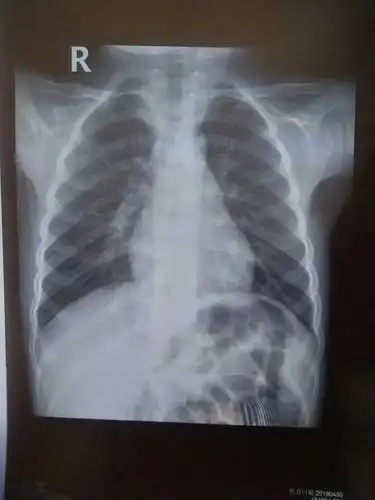

一张小孩胸片,请帮忙看看.

大家来看看这张小孩子 的胸片

用了退热贴,就降下来了,第二天去医院,拍的胸片医生说严重支气管肺炎